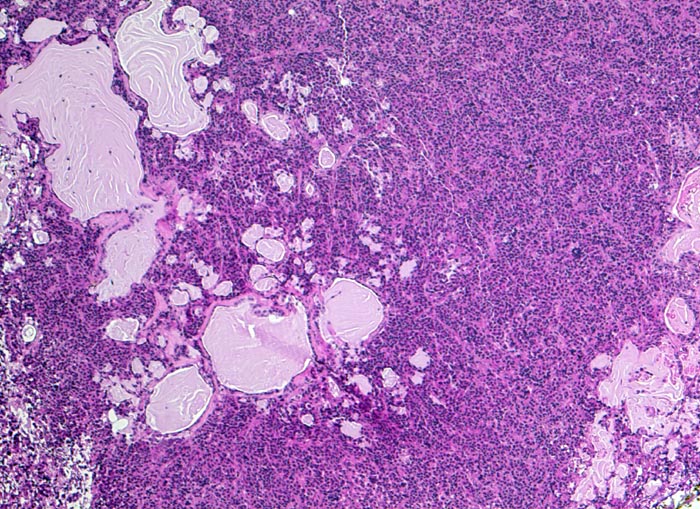

diffus wachsendes chromophobes Hypophysenadenom

Vereinzelte epithelialisierte Zysten, sehr wahrscheinlich der Pars intermedia entsprechend. Daneben ein diffuses Tumorinfiltrat aus kleinen zytoplasmareichen Zellen.

Expression von Prolactin in 100% der Tumorzellen (Prolactinom), herdförmiger Expression von ACTH in isolierten Zellen und in vereinzelten Tumorzellverbänden. Expression von Beta-TSH in isolierten Tumorzellen. MIB-1-Index weit unter 1%.

Hypophysenmakroadenom mit erhöhtem Prolaktinspiegel